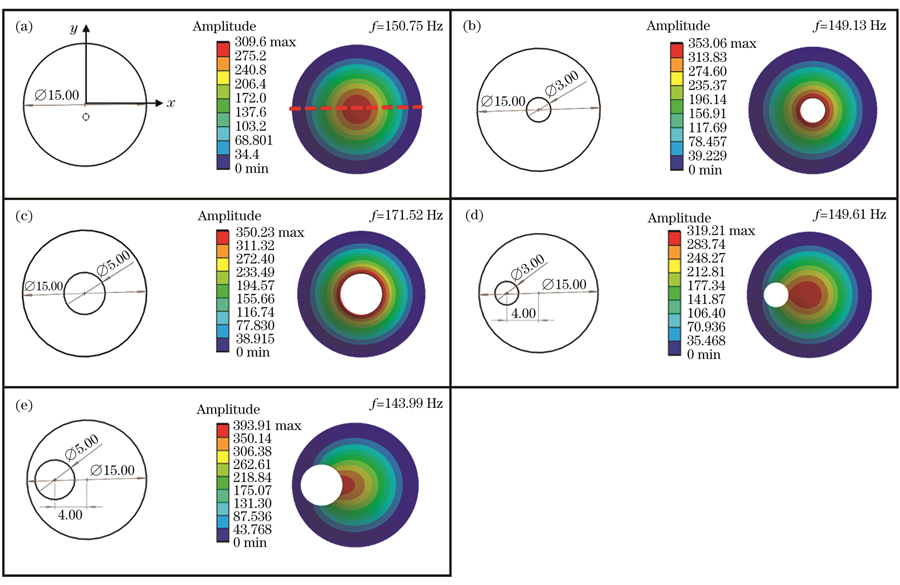

在薄膜上设置圆形缺陷来模拟耳膜穿孔。

图 3. 穿孔薄膜一阶振动模态的仿真结果。(a)无缺陷薄膜;(b)中心穿孔3 mm薄膜;(c)中心穿孔5 mm薄膜;(d)偏心穿孔3 mm薄膜;(e)偏心穿孔5 mm薄膜

Fig. 3. Simulation results of first-order vibration modes of perforated films. (a) Defect-free film; (b) film with a 3 mm diameter perforation in the center; (c) film with a 5 mm diameter perforation in the center; (d) film with an eccentric 3 mm diameter perforation; (e) film with an eccentric 5 mm diameter perforation

图 4. y=0处的振幅分布截面图。(a)中心穿孔薄膜;(b)偏心穿孔薄膜

Fig. 4. Section of amplitude at y=0. (a) Central perforated film; (b) eccentric perforated film

如

First, the theoretical analysis proves that using the spatial carrier phase extraction method to detect the amplitude distribution in eardrum samples in the vibration mode is reasonable. In the finite element simulation and experimental analysis, the vibration modes of the artificial eardrums with defects were analyzed, and the results showed that different defects affect the amplitude distribution in the first-order vibration mode for the eardrums differently. For the perforated eardrum samples, the amplitude distribution was analyzed by varying the size and location of the perforation. The results show that the amplitude near the perforation increases significantly with the increase in perforation size (Figs. 3 and 4), and an increase in the number of fringes is observed in the experimental results (Fig. 11). By changing the location of the perforation, the maximum amplitude shifts off-center with the perforation, and the larger the perforation, the more evident the deviation. The amplitude distribution for the scratched eardrum samples was analyzed by varying the size and location of the scratch. The results show that at the same location, the larger the scratch length, the larger the surface amplitude of the film (Fig. 5), and the amplitude changes more significantly near the scratch location (Fig. 6). The experimental results show an increase in the number of fringes, and the shape of the fringe near the central scratch is flat (Fig. 12). When the scratch is off-center, the effect on the amplitude near the scratch is significantly greater than that at the center. The amplitude distribution for the calcified eardrum samples was analyzed by varying the thickness of the calcified layer (Fig. 7). The amplitude of the film decreases with an increase in the thickness of the calcified layer but is more evident at the location of the calcified layer (Figs. 8 and 13).